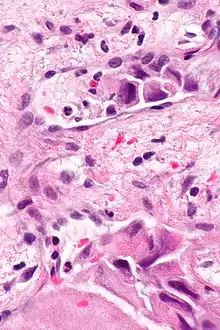

Lymphovascular invasion

Lymphovascular invasion (LVI or lymphovascular space invasion) is the invasion of a cancer to the blood vessels and/or lymphatics.

Lymphovascular invasion, especially in carcinomas, usually precedes spread to the lymph nodes that drain the tissue in which the tumour arose. Conversely, cancers with lymph node spread (known as a lymph node metastases), usually have lymphovascular invasion. Lymph node metastases usually precede secondary tumours, i.e. distant metastases.